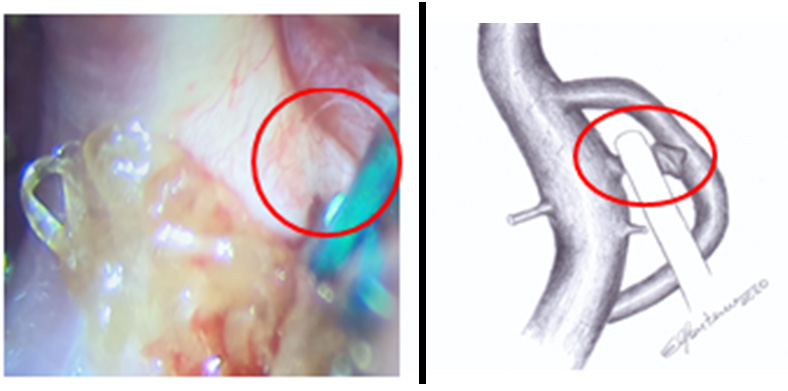

We chose to use a mini clip to laterally decrease the infundibular dilation. Upon releasing the clip, we evidenced not an infundibulum, but a typical aneurysm, with the posterior communicating artery well attached to its wall, which was released and exposed at the time of this clipping (Figure 5).

Figure 5: Individualization of the posterior communicating artery and clipped aneurysm.